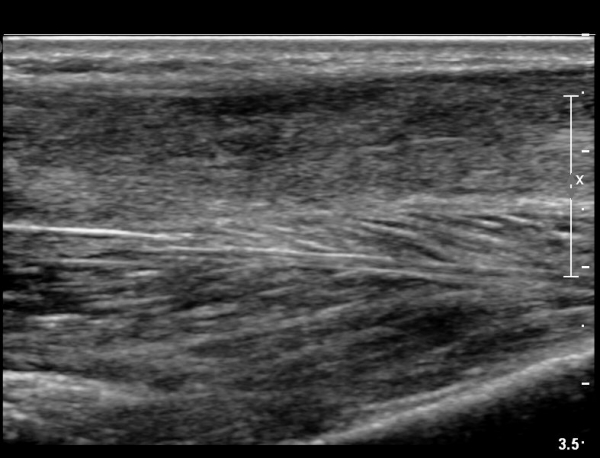

¾ÆÅ³·¹½º°Ç ±ÙÀ§ºÎ Á¾´Ü¸é°Ë»ç¿¡¼­ ¾ÆÅ³·¹½º°ÇÀÇ Àú¿¡ÄÚºÎÁ¾, ±¹¼ÒÀû ¿¬°á¼º ¼Ò½ÇÀÌ °üÂûµÇ¾î

ÆÄ¿­ÀÌ ±¤¹üÀ§ ÇÑ °ÍÀ» º¸¿©ÁÜ(»çÁø 6, 7).